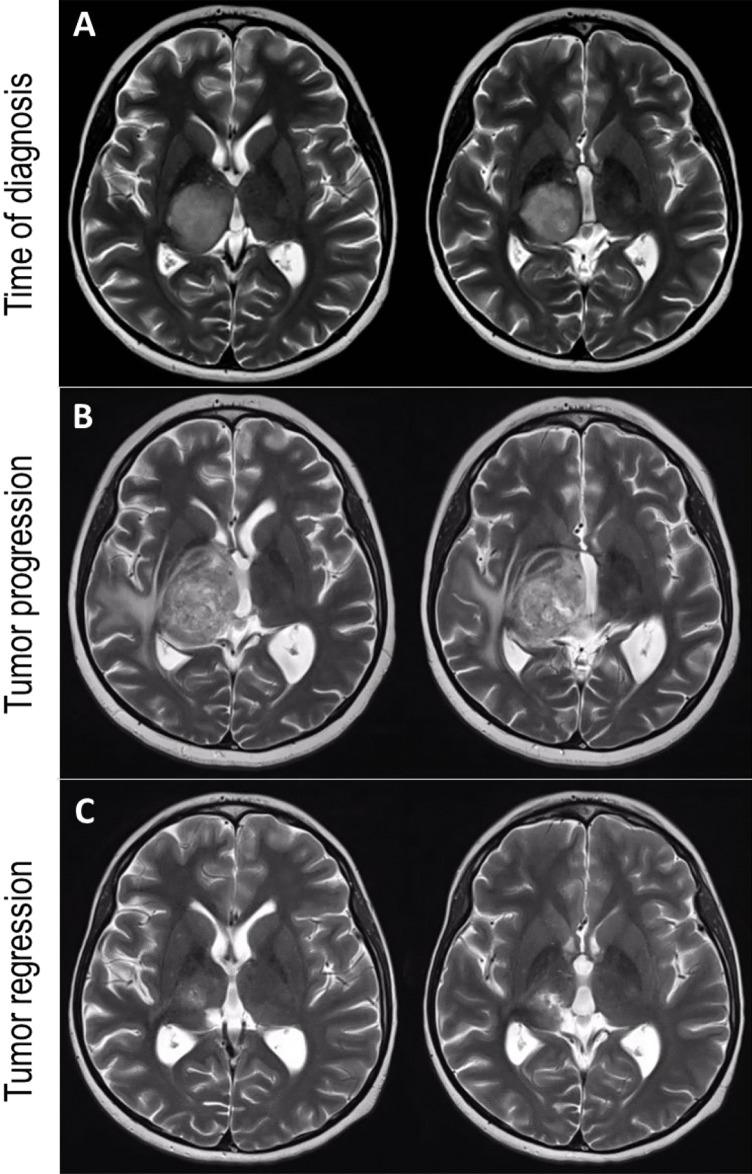

We report on a 11-year-old boy who complained of hypaesthesia and fine motor problems in the left hand. A magnetic resonance imaging showed a large mass in the right thalamus. Stereotactic biopsy revealed a WHO grade 4 astrocytoma, and the patient underwent normofractioned radiochemotherapy with proton-beam radiation and temozolomide. Three months later, a spastic hemiparesis developed on the left side, which progressed over months. Over the following months, the hemiparesis slowly improved, but hemidystonia in the same side developed. This was accompanied with radiological evidence of tumor regression, showing a persistent lesion in the ventral posterolateral and the intralaminar thalamus.

This case illustrates the unusual and complex temporal course of appearance and disappearance of hemidystonia along with the regression and growth in glioblastoma involving the thalamus.